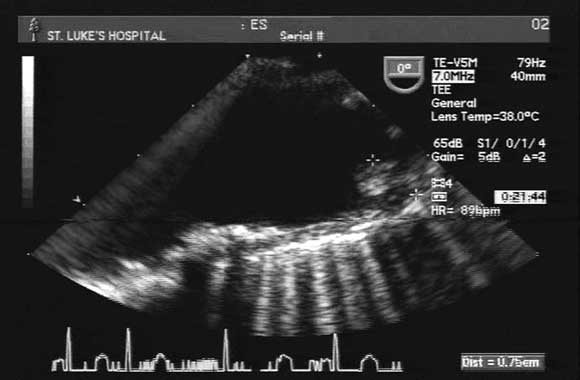

A transoesophageal echogram showed normal cardiac and valve function, with no obvious thrombi. However, there were diffuse atherosclerotic changes in the aortic arch, with a grade-IV protruding atheroma (7 mm) proximal to the innominate artery (Box). An arterial Doppler study of both upper extremities showed a lack of flow in the right ulnar artery.